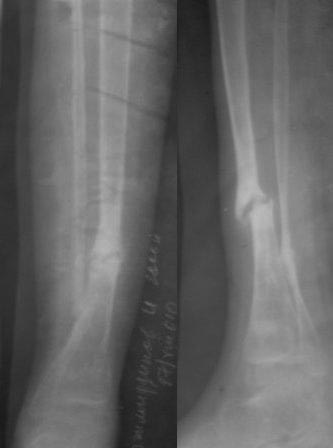

Уважаемые коллеги! помогите советом! Мальчик 2000 г.р. В 2007г получил

перелом н/з костей правой голени,

в районе лечили гипсом 6 месяцев, сращения нет, в обл.центре КДО

аппаратом Илизарова - 3 месяца, после повторная деформация, в НИИТО КДО

аппаратом Илизарова -7 месяцев, перелом якобы сросся, но после снятия

аппарата через 2 недели после незначительной травмы повторный перелом. И

нога сильно атрофировалась.(Мне кажется у ребенка был врожд. ложный

сустав, латентная форма) , и в 2011 г, в октябре обратились к нам. ,

выписали, повторно приехали только ч-з 1,5 года вот с такой деформацией,

но ребенок ходит в школу, бегает, незначительно хромает, родители

требуют исправить деформацию.